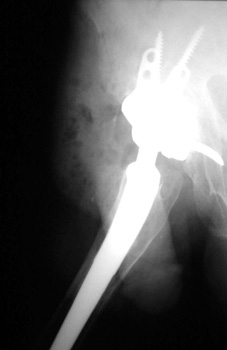

Revision arthroplasty with long femoral stem and large phalanged cup. Note inguinal hernia containing bowel.